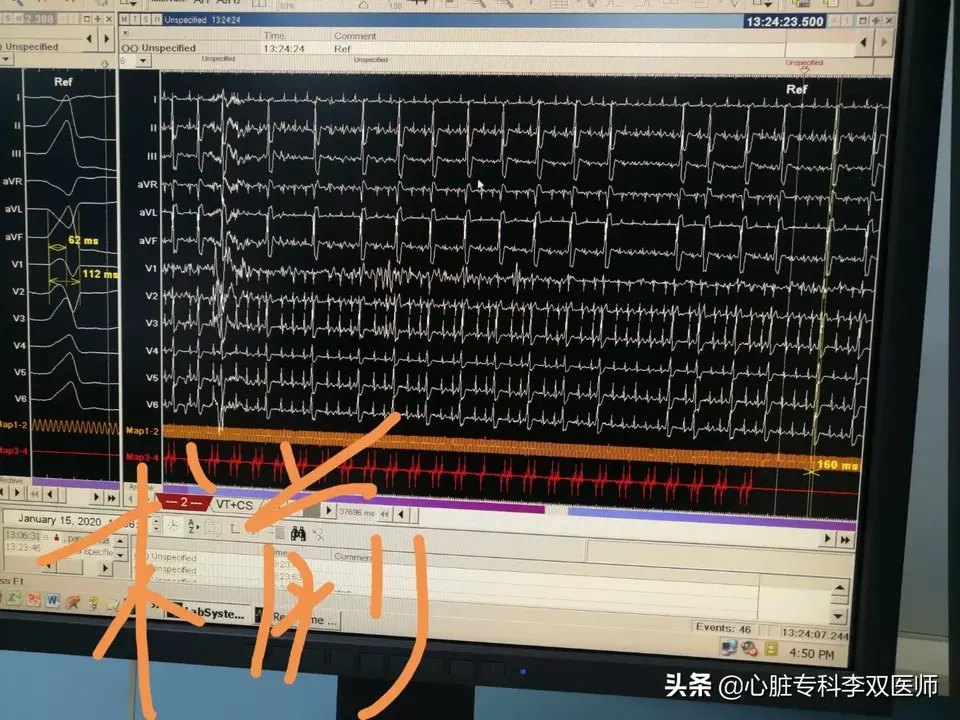

前天给一个外地来就诊的病人做了难度很高的“心外膜室早”消融的病例,病人一年前在杭州某三甲医院曾行消融失败,这一年来因为笼罩在“频发室早”的阴影下,患者有了明显的心理问题。这次我们标测的情况和上次外院消融情况完全一致,只是坚持又带有一点运气的在非传统的消融位置(解剖位置,而不是最早激动位置)尝试了消融,结果异常的顺利,术中忐忐忑忑观察了一小时无复发。今天患者顺利出院,术后24小时心电图提示的室早仅2次(一天的心跳是约10万次,1000次以内的早博没有意义),比机器的误差都小,而术前是1.4—2.8万次,是万!万!万!。坚持就是胜利,坚持带来好运!